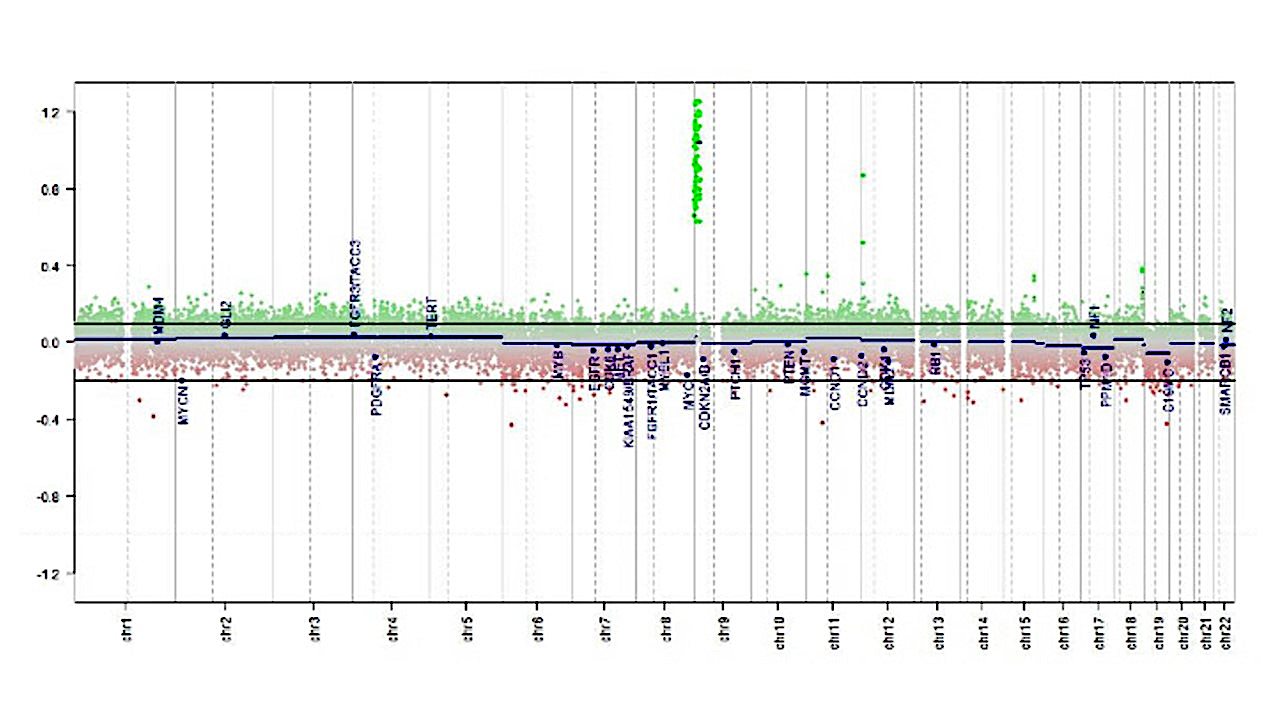

Molecular / cytogenetics description

- The following 3 methylation classes of choroid plexus tumors are recognized based on the German Cancer Research Center (DKFZ) Heidelberg classification:

- Plexus tumor, subclass adult

- Plexus tumor, subclass pediatric A

- Plexus tumor, subclass pediatric B (closely related to methylation cluster 3 described in Neuro Oncol 2016;18:790)

- TP53 sequencing and testing for germ line TP53 mutation is advisable in children with choroid plexus carcinoma

Molecular / cytogenetics images

- Methylation class: Plexus tumor, subclass pediatric B, family class PLEX_T

- Molecular tests (sequencing): No TP53 mutation

- Comment: The tumor shows moderate atypia, histologically equivalent to WHO grade 2. The methylation array has classified as subclass B, which is closely related to methylation cluster 3 described in Neuro Oncol 2016;18:790.